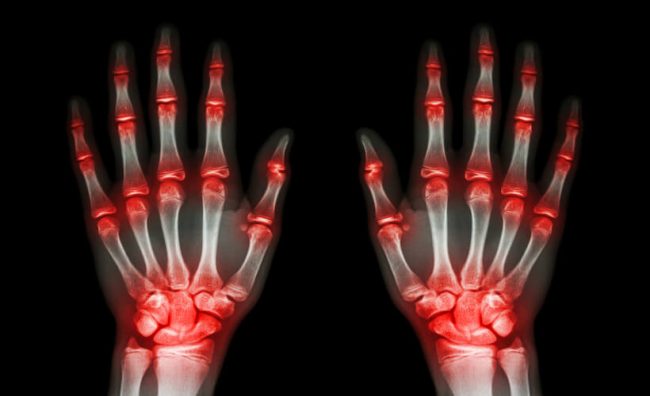

La patología reumatológica es tratada por especialistas traumatólogos, que se encargan de prevenir, diagnosticar y tratar las enfermedades musculoesqueléticas y autoinmunes sistémicas. Y hay más de 200 enfermedades reumáticas que pueden afectar a cualquier edad. Estas enfermedades afectan a uno de cada cuatro adultos en España, convirtiéndola en la segunda causa de consulta, tras las…